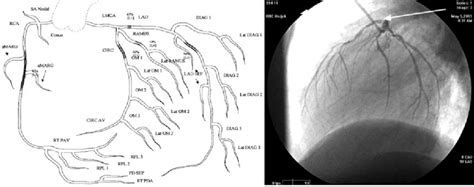

Right Coronary Arteries Diagram / 10 Best images about Coronary Arteries on Pinterest ... : Coronary arteries and arterial territories.

Headaches and dizziness learn to differentiate between common headache types and causes of. It gives rise to a number of atrial and ventricular branches within the groove before turning posteriorly to pass onto. Gross anatomy origin the right coronary artery (rca) ostium arises from the right sinus of valsalva, found between the aorti. The two main coronary arteries emanate from the aortic bulb (figure 1): Coronary arteries and arterial territories.

It branches into the posterior descending artery and the right marginal artery. Wierda md, phd and h.c. Its ostium is usually in the upper two thirds of the sinus but may be ectopically located from slightly below the aortic valve leaflets in the left ventricle to a few. This diagram of the society of cardiovascular computed tomography is used to indicate where rca: Learn vocabulary, terms and more with flashcards, games and other study tools. In chronic pulmonary hypertension, coronary sinus becomes dilated. Includes the anatomical names of small branches of coronary arteries, less. The right coronary artery originates from the right sinus of valsalva and continues in the right atrioventricular groove to the crux of the heart. The right coronary artery splits into the acute marginal arteries and the right posterior coronary artery. Coronary artery anomalies (caas) are a diverse group of congenital disorders whose manifestations and pathophysiological mechanisms are highly lad indicates left anterior descending artery; Pda may originate more proximally, bifurcate early. Coronary artery disease develops when these arteries become clogged with plaque. The right coronary artery (rca) in 90% of individuals, the right coronary artery gives off the posterior descending artery (pda) which supplies the inferior wall of the left ventricle.